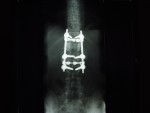

He has TWO rods in his back for support up and down... Two screws at the bottom of each rod and one at the top... He is in recovery at this time more than likely still...

He Faces a LONG three to Four months of bed rest while his back heals up... The Best of luck in all of this. The Doctors were able to do ALL of the surgery through his THIN little body Via his BACK and Did not have to cut his chest etc at all... He has 2 rods in his back and that is NOW confirmed and what I posted last night late is all good...

The hardware is coming out! On April 28th I'm gettin' this monkey off (out of) my back. Hopefully it is the source of the leg pain that has slowed the recovery process.

- The Monkey